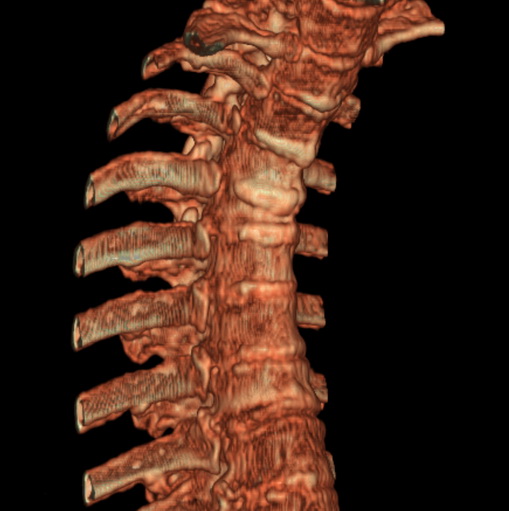

女、73、胸痛、胸闷3个月,无明显外伤病史,x线疑t4、t7陈旧压缩骨折,ct未经明显骨折,请问结论如何报?

老年女性病人,骨质稀疏,有些驼背,t4明显变扁,t7略变扁,椎体边缘无中断,骨小梁排列正常,无嵌插所致致密线。结合无明显外伤史,考虑老年骨质稀疏,慢性压缩改变,正如老年人骨质稀疏椎体呈双凹改变一样。我考虑报:老年骨质稀疏,t4、t7楔形变,脊柱曲度改变(驼背).敬请大家指教。